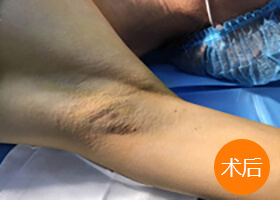

案例见证

湖南附大腋臭专科水刀腋臭手术现场观摩

Bad smell surgery scene to observe the meeting为了给广大腋臭患者更真实更直观的了解水刀祛臭效果,湖南附大腋臭专科不定期举行腋臭手术观摩会。观摩会嘉宾都是湖南附大腋臭专科的真实案例,欢迎广大腋臭患者在线预约与观摩嘉宾零距离交流,零剪辑感受祛臭效果!